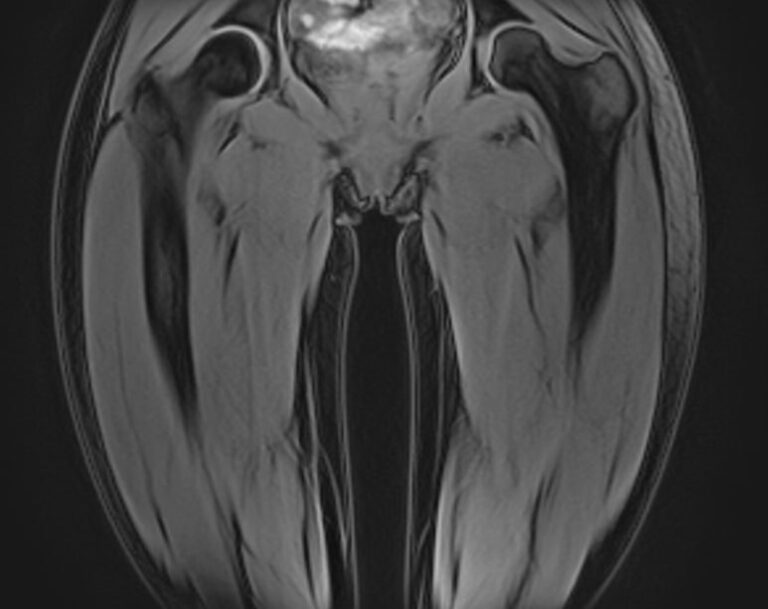

Скрининговое обследование всего тела с помощью метода магнитно-резонансной томографии включает в себя сканирование головы, шеи и туловища с органами брюшной полости, забрюшинного пространства и малого таза.

В нашей клинике МР-скрининг всего тела проводится на новейшем высокопольном томографе экспертного класса TOSHIBA VANTAGE TITAN 1,5 Тесла. Аппарат послойно сканирует структуры всего тела в различных плоскостях в виде тончайших срезов с шагом от 1 мм, затем посредством инновационных компьютерных программ преобразует полученные данные в трехмерные изображения превосходного качества.